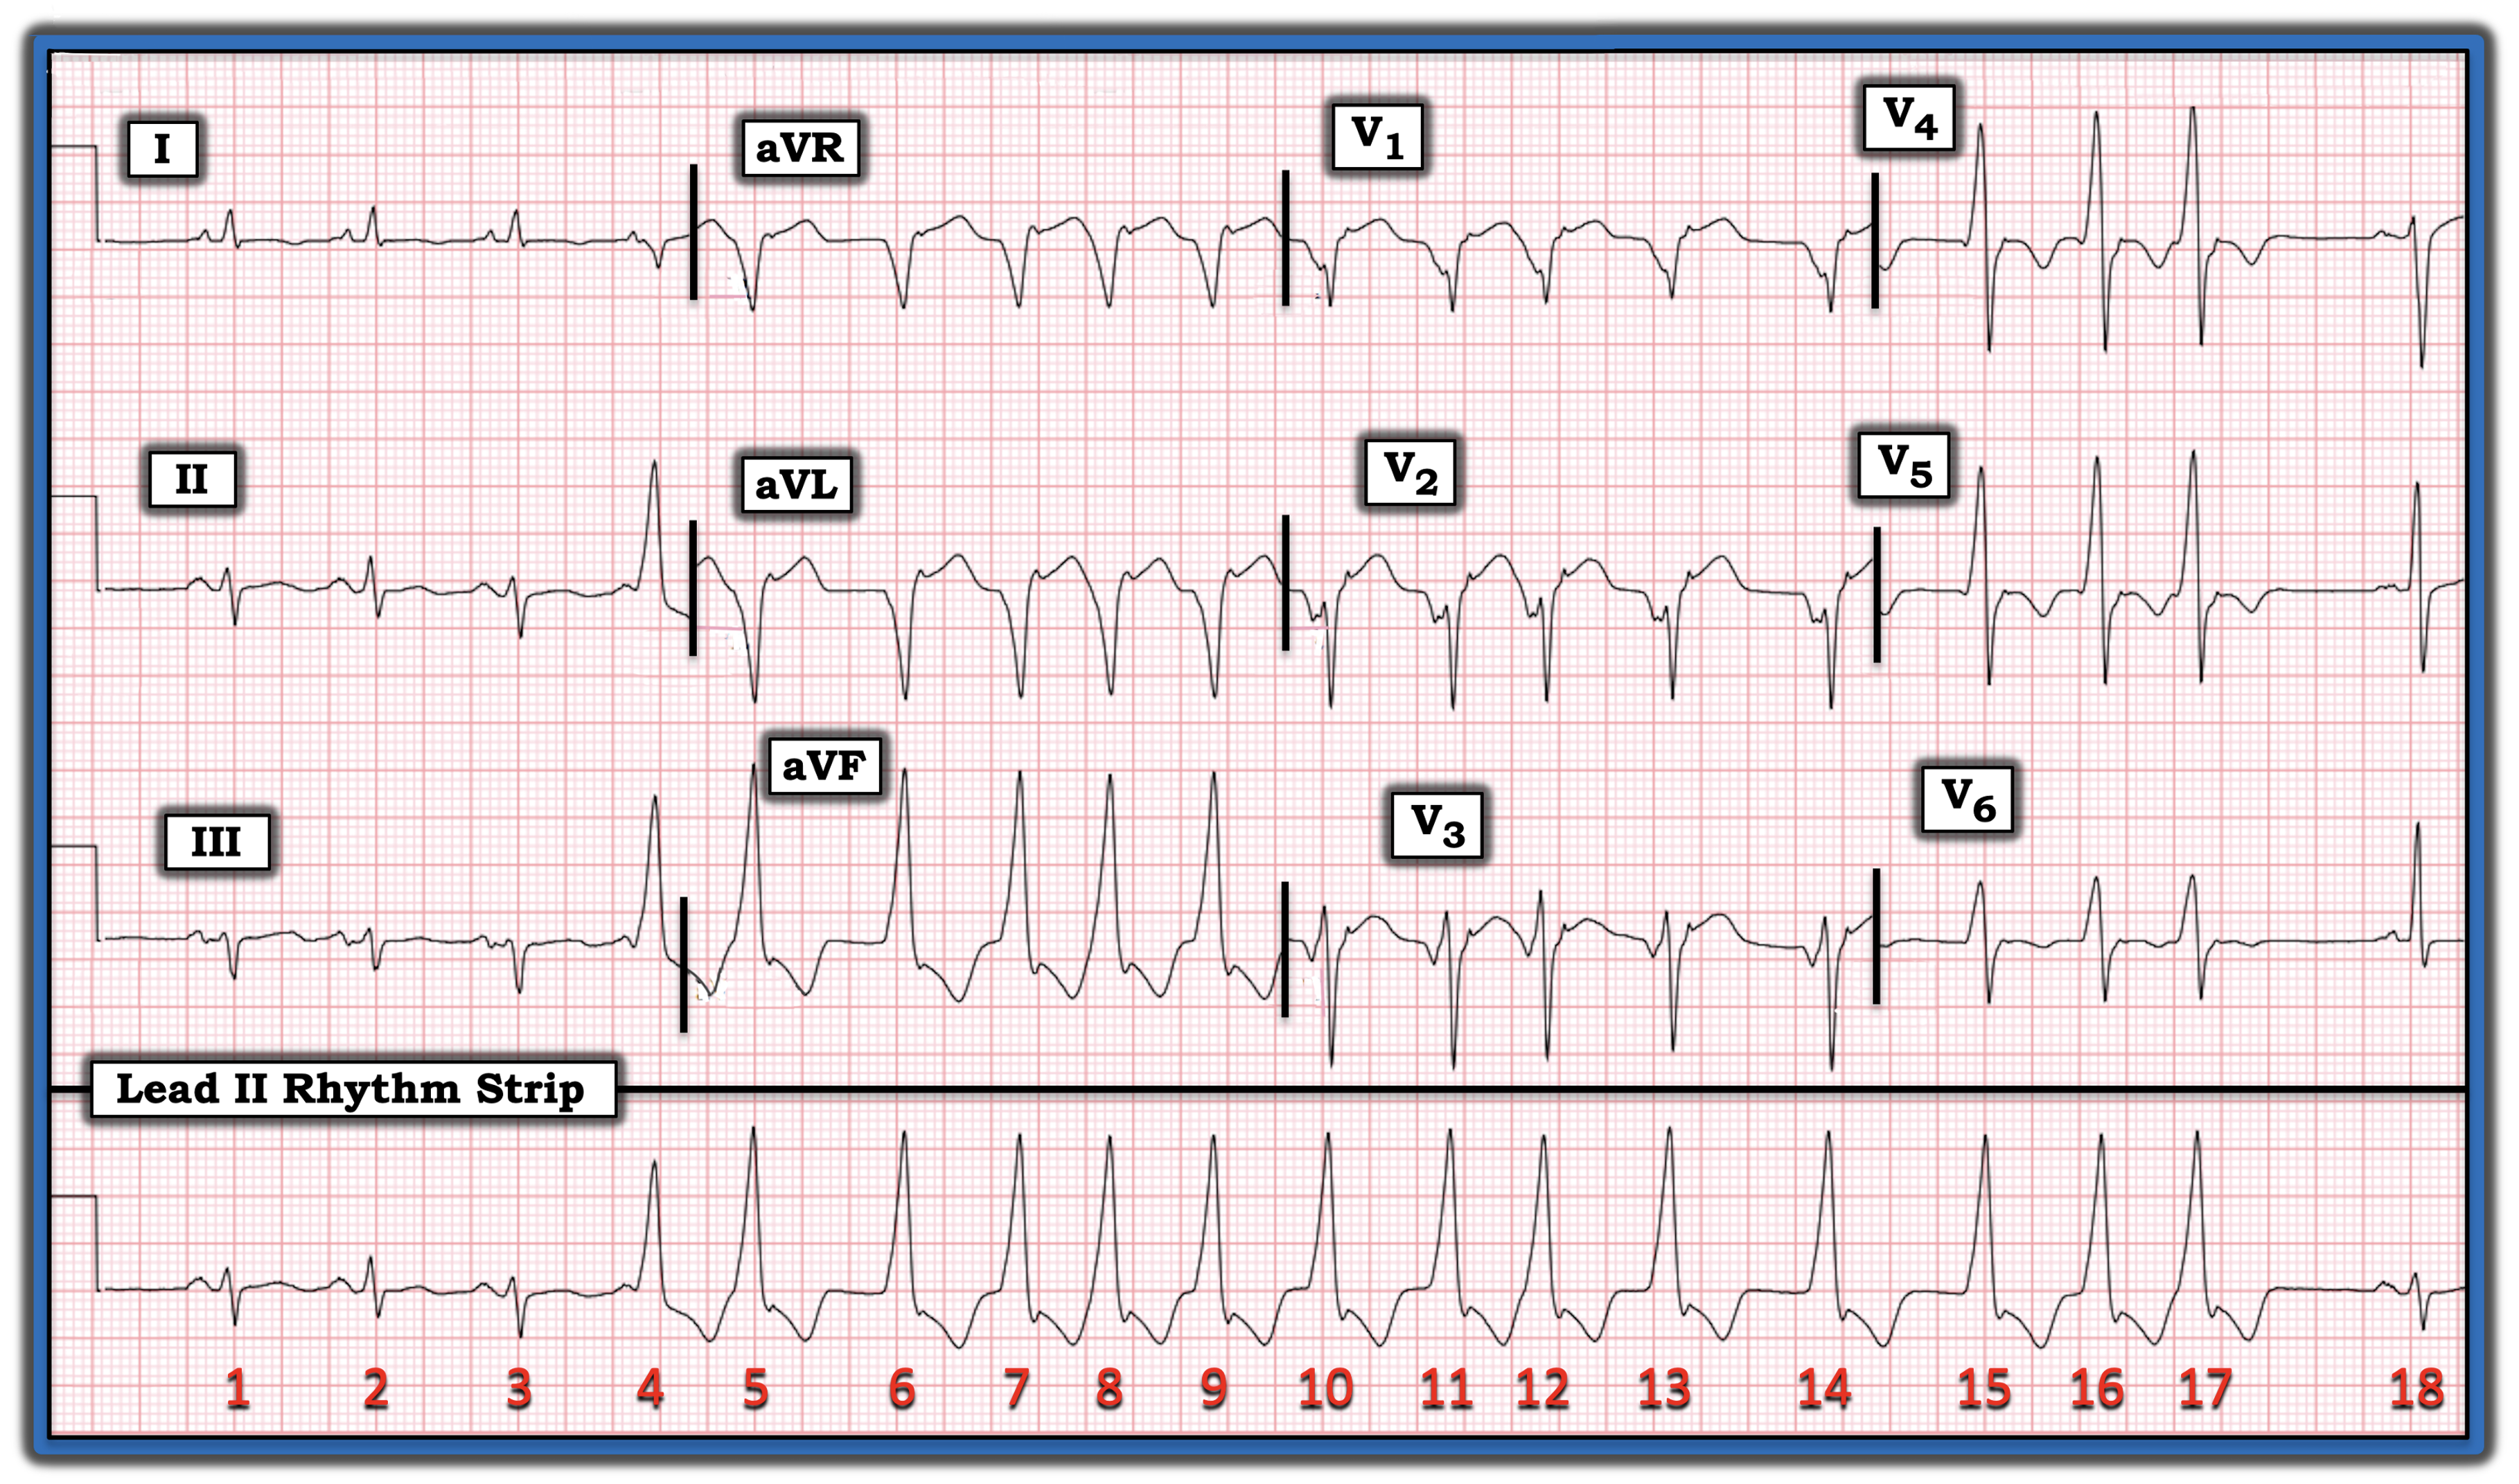

The patient whose electrocardiogram (ECG) appears in the figure is a previously healthy man who presented to the emergency department because of acute dyspnea. What is the cause of the run of wide beats?

Interpretation: As always, I favor at least a brief look at the simultaneously recorded long lead rhythm strip before shifting my attention to the 12-lead ECG.

This tip is especially helpful in today’s case because assessment of ST-T wave morphology is less reliable in leads in which the QRS complex is wide.

- As a result — assessment of ST-T wave morphology will be reliable only for beats 1, 2, and 3 in simultaneously recorded leads I, II, and III. These leads show three initial beats of sinus rhythm with marked left axis deviation (consistent with left anterior hemiblock), and nonspecific ST-T wave changes — but do not suggest anything acute.

- The final QRS complex in today’s ECG is a narrow, sinus-conducted beat ( = beat #18), but the tracing ends before we see the ST-T wave of this last beat.

Regarding today’s rhythm — after three narrow, sinus-conducted beats — the QRS complex widens, and remains wide from beat #4 until beat #17.

- Note that the rhythm is irregularly irregular during this run of 14 wide beats (from beat #4 until beat #17).

- Although the irregular irregularity of these 14 wide beats suggest atrial fibrillation, this is not the etiology because the first wide beat (beat #4) has a relatively long coupling interval, such that there is no reason for sudden development of aberrant conduction (which usually is seen in association with a short coupling interval) and beat #4 is a fusion beat!

- Note that the beginning of an on-time sinus P wave is seen just before the beginning of the QRS complex of beat #4. The PR interval of beat #4 is, therefore, too short to conduct normally.

- Note also that R wave amplitude of beat #4 is slightly shorter than R wave amplitude of the 13 wide beats that follow. This is not by chance — but instead reflects that there is “fusion” between beginning conduction of the on-time sinus P wave before beat #4 — and the first beat in this 14-beat run of ventricular tachycardia VT!

- Recognition of the fusion beat proves that the run of wide beats in this tracing is VT. And although monomorphic VT usually is a regular rhythm — today’s case shows that it may sometimes be irregular!